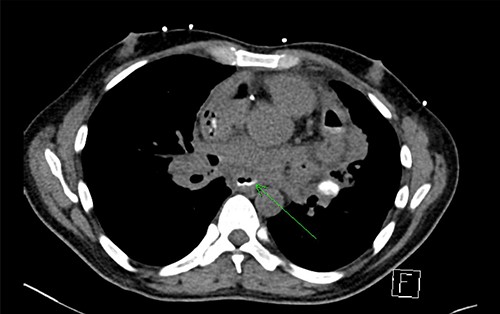

An OPF was confirmed on chest CT with water-soluble oral contrast. Endoscopy demonstrated three mucosal defects 31 cm from the incisors (Fig. 3). A fully-covered WallFlex stent (23 × 15 mm, Boston Scientific) was positioned to cover the OPF. The stent was secured proximally to the oesophageal mucosa using resolution clips and distally to the stomach using a 3–0 PDS trans-gastric suture placed laparoscopically. The patient improved and it was decided not to proceed with pericardial drainage.

Upper gastrointestinal endoscopy demonstrated three mucosal defects 31 cm from the incisors.